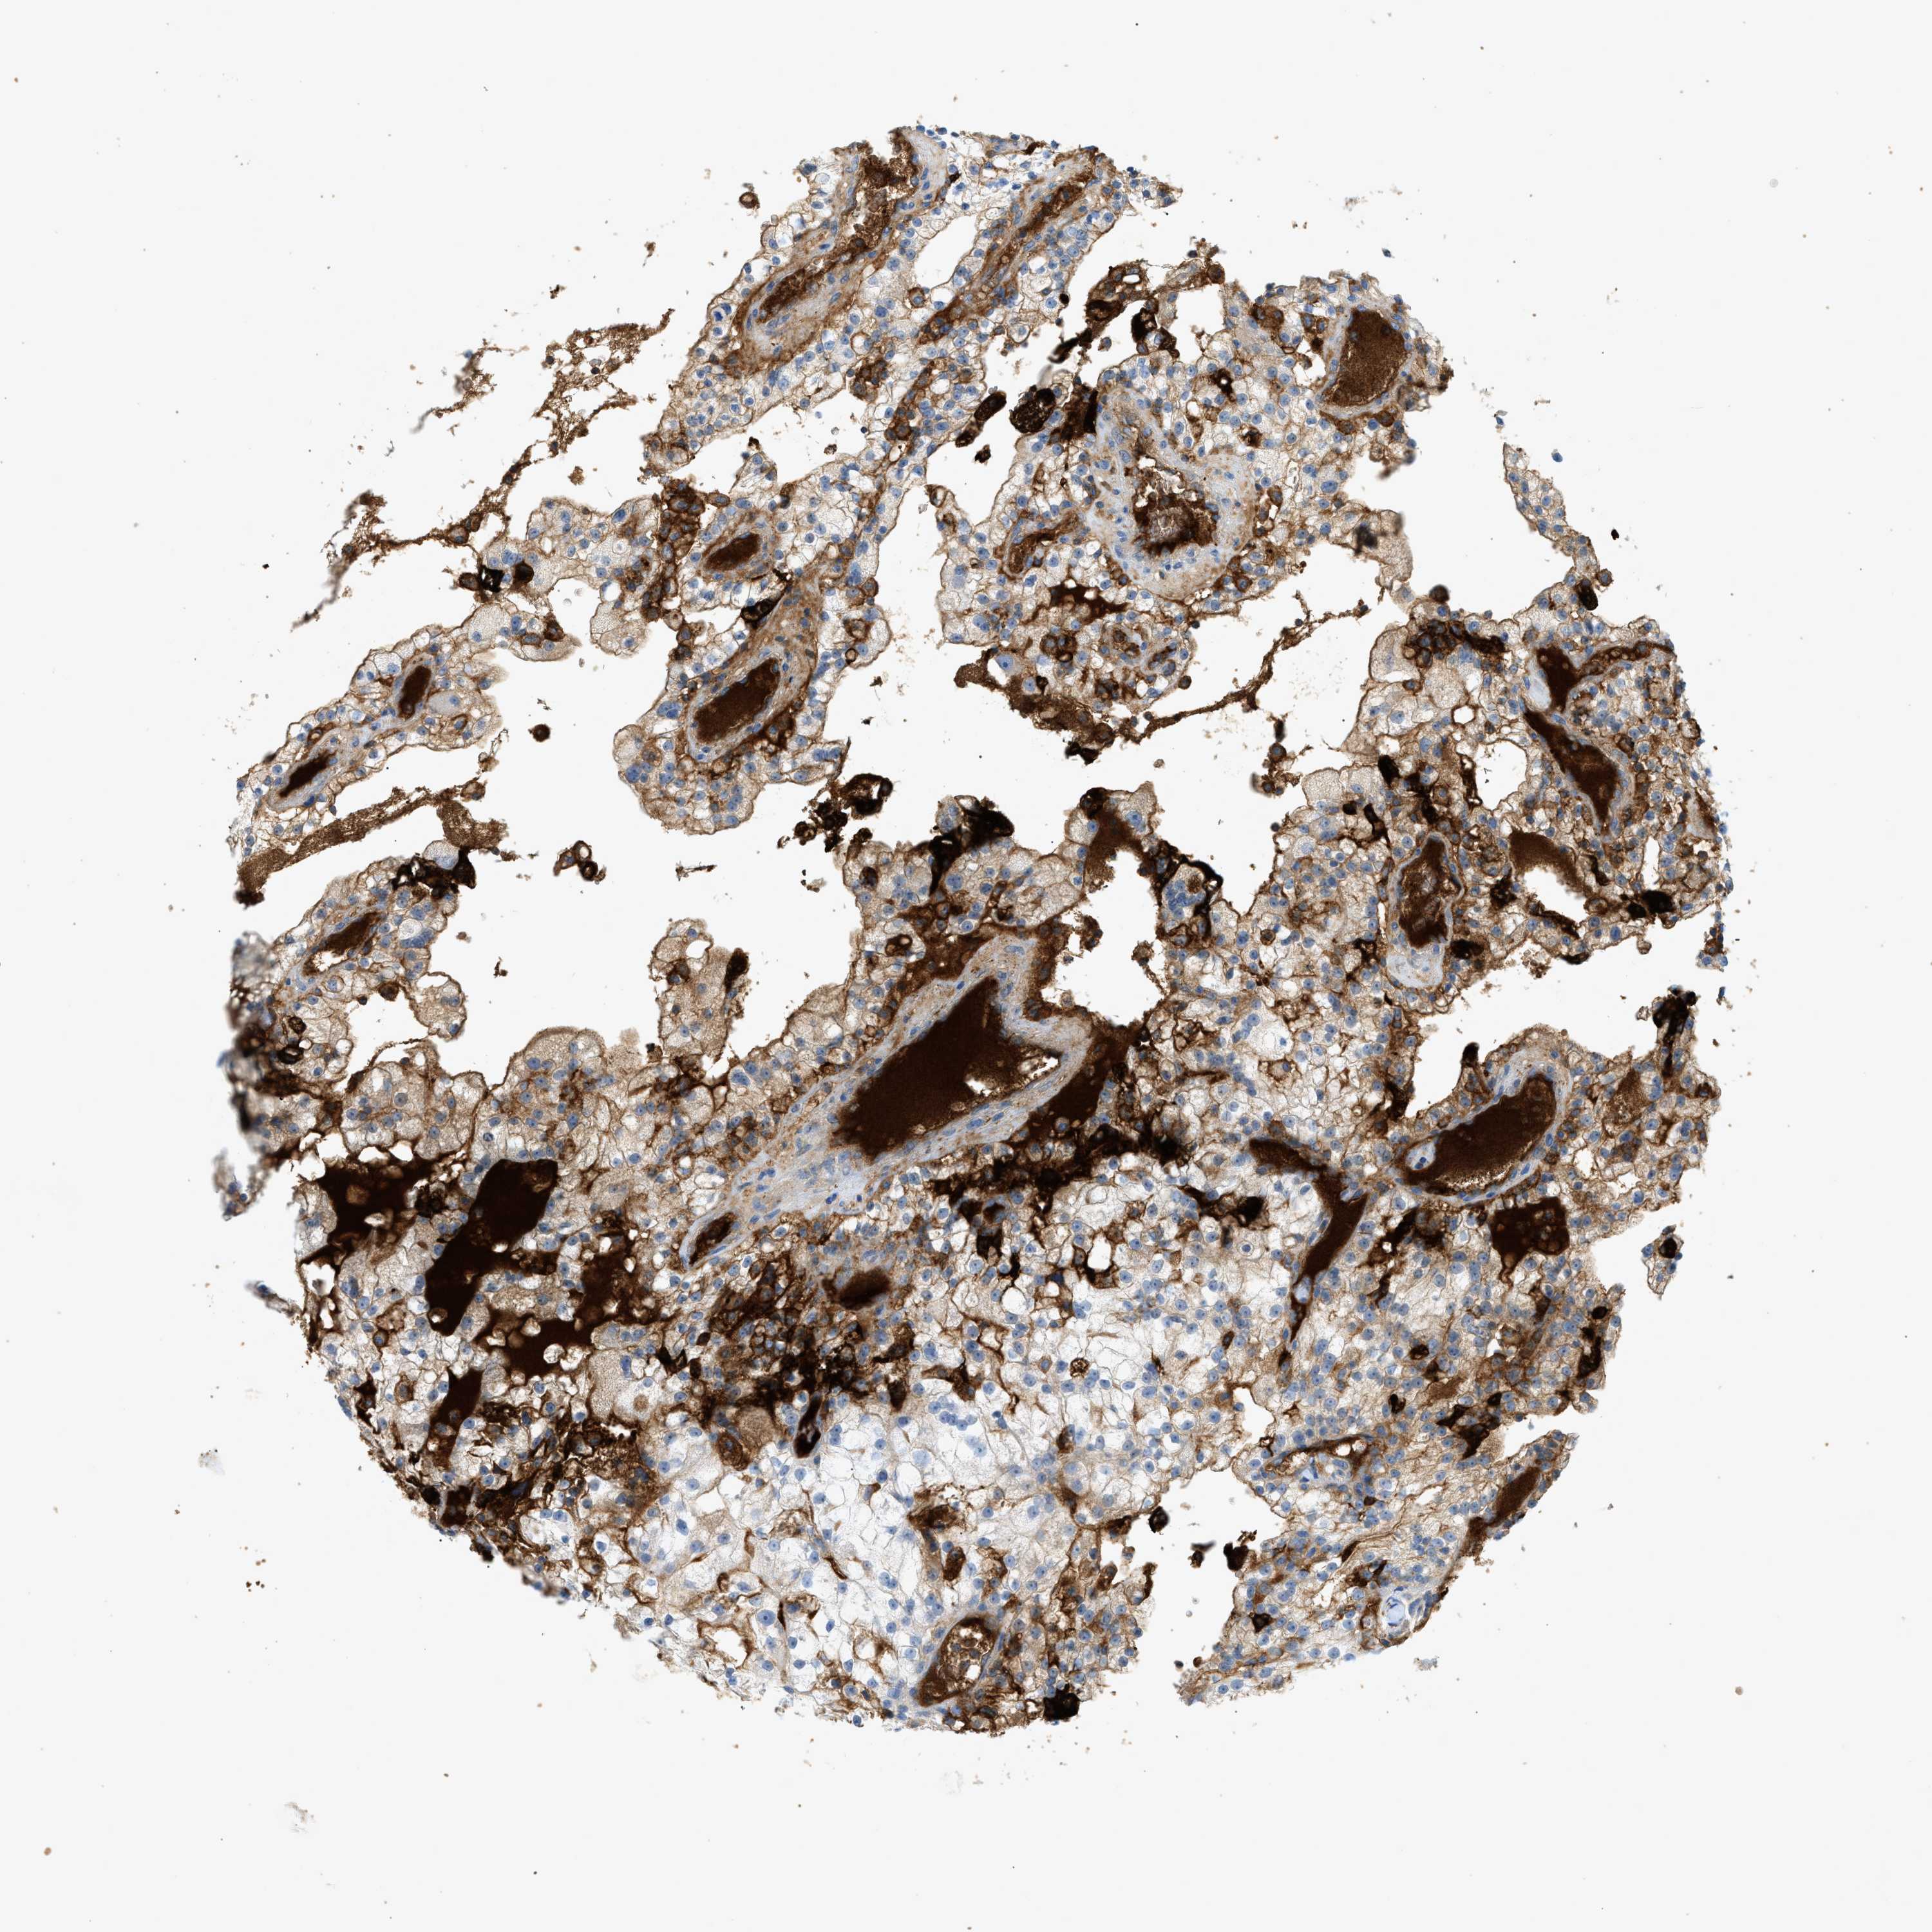

KIDNEY RENAL CLEAR CELL CARCINOMA (TCGA) - Interactive survival scatter ploti

The Survival Scatter plot shows the clinical status (i.e. dead or alive) for all individuals in the patient cohort, based on the same data that underlies the corresponding Kaplan-Meier plots. Patients that are alive at last time for follow-up are shown in blue and patients who have died during the study are shown in red.

The x-axis shows the expression levels (FPKM) of the investigated gene in the tumor tissue at the time of diagnosis. The y-axis shows the follow-up time after diagnosis (years). Both axes are complimented with kernel density curves demonstrating the data density over the axes. The top density plot shows the expression levels (FPKM) distribution among dead (red) and alive patients (blue). The right density plot shows the data density of the survived years of dead patients with high and low expression levels respectively, stratified using the cutoff indicated by the vertical dashed line through the Survival Scatter plot. This cutoff is automatically defined based on the FPKM cutoff that minimizes the p-score. The cutoff can be changed by dragging the vertical line or by entering a cutoff value in the square labeled "Current cut-off".

Under the Survival Scatter plot the p-score landscape (black curve; left axis) is shown together with dead median separation (red curve; right axis). Dead median separation is the difference in median mRNA expression between patients who have died with high and low expression, respectively. It is calculated as follows: median FPKM expression of dead patients with high expression - median FPKM expression of dead patients with low expression. This is intended to aid the user in visually exploring custom cutoffs and the associated p-scores and dead median separation.

Individual patient data is displayed and can be filtered by clicking on one or more of the category buttons on the top of the page. Categories describing expression level and patient information include: high, low, alive, dead, female, male and tumor stages. The scale of the x-axis can be toggled between linear and log-scale by clicking on the "x log" button. Mouse-over function shows TCGA ID, patient information and mRNA expression (FPKM) for each patient.

& Survival analysisi

Kaplan-Meier plots summarize results from analysis of correlation between mRNA expression level and patient survival. Patients were divided based on level of expression into one of the two groups "low" (under cut off) or "high" (over cut off). X-axis shows time for survival (years) and y-axis shows the probability of survival, where 1.0 corresponds to 100 percent.

F2 is validated prognostic, high expression is unfavorable in Kidney Renal Clear Cell Carcinoma (TCGA)

Best expression cut offi

: 0.47

TCGA RNA samplesi

RNA-seq data is reported as average FPKM (number Fragments Per Kilobase of exon per Million reads), generated by the The Cancer Genome Atlas (TCGA) .

Normal distribution across the dataset is visualized with box plots, shown as median and 25th and 75th percentiles. Points are displayed as outliers if they are above or below 1.5 times the interquartile range. FPKM values of the individual samples are presented next to the box plot.

Average pTPM 4.2

Number of samples 521